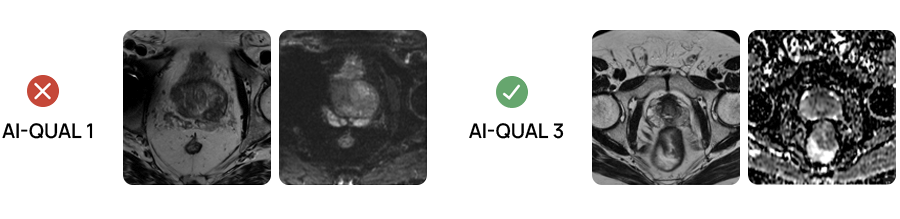

Image quality assessment

Quibim AI-QUAL™ automates the assessment of prostate MRI image quality based on the PI-QUAL v2 guidelines.

AI-QUAL™: Automated Prostate Image Quality Assessment

Quibim’s AI-QUAL™ automates the assessment of prostate MRI image quality based on the PI-QUALv2 guidelines. This tool streamlines workflows and supports diagnostic confidence.

Key benefits of AI-QUAL include:

- Automated Quality Scoring: Eliminates manual checks, saving time and reducing subjectivity.

- Standardized Reporting: Delivers consistent quality score based on PI-QUAL v2 guidelines.

- Artifact Detection: Identifies key image-degrading factors such as rectal gas distortion and metal artifacts.

- Diagnostic Confidence: Ensures radiologists work with the highest quality images.

- Seamless Integration: Designed to fit effortlessly into existing radiology workflows.